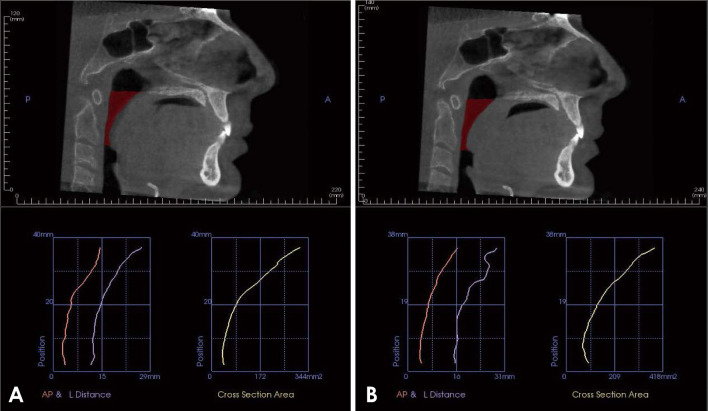

Materials and methods: Forty patients with obstructive sleep apnea were selected from the ear-nose-throat (ENT) outpatient clinic, Faculty of Medicine, Mansoura University. Cone-beam computed tomography was performed for each patient at the end of both inspiration and expiration. Polysomnography was carried out, and the apnea-hypopnea index was obtained. Linear measurements, including cross-sectional area and the SNA and SNB angles, were obtained. Four oral and maxillofacial radiologists categorized pharyngeal and retropalatal airway morphology and calculated the airway length and volume. Continuous data were tested for normality using the Kolmogorov-Smirnov test and reported as the mean and standard deviation or as the median and range. Categorical data were presented as numbers and percentages, and the significance level was set at P<0.05.

Results: The minimal value of the cross-sectional area, SNB angle, and airway morphology at the end of inspiration demonstrated a statistically significant association (P<0.05) with the apnea-hypopnea index, with excellent agreement. No statistically significant difference was found in the airway volume, other linear measurements, or retropalatal airway morphology.